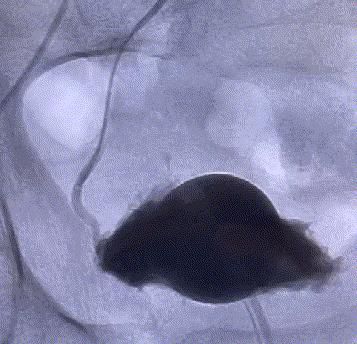

随後,李旭丹主任攜手胡志華主任爲患者實施介入治療,采用改良Seldinger法穿刺股動脈,在DSA引導下經動脈自然腔道,将微導管分别送達雙側髂内動脈進行造影,觀察雙側前列腺動脈分布情況,将微導管超選擇至雙側前列腺動脈,準确置入PVA栓塞材料,成功阻斷前列腺的營養供給,順利完成了治療。

△術前,可見前列腺供血豐富。

△術後,前列腺供血動脈被成功阻斷。